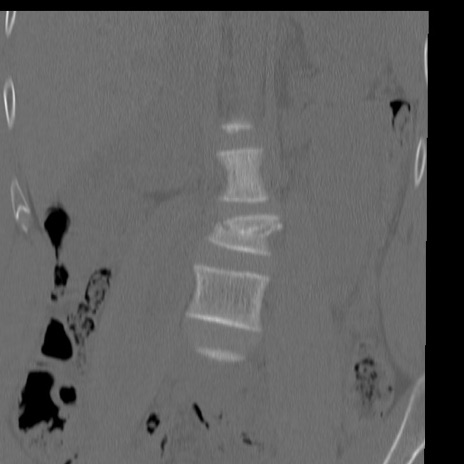

腰椎CT

矢状断像